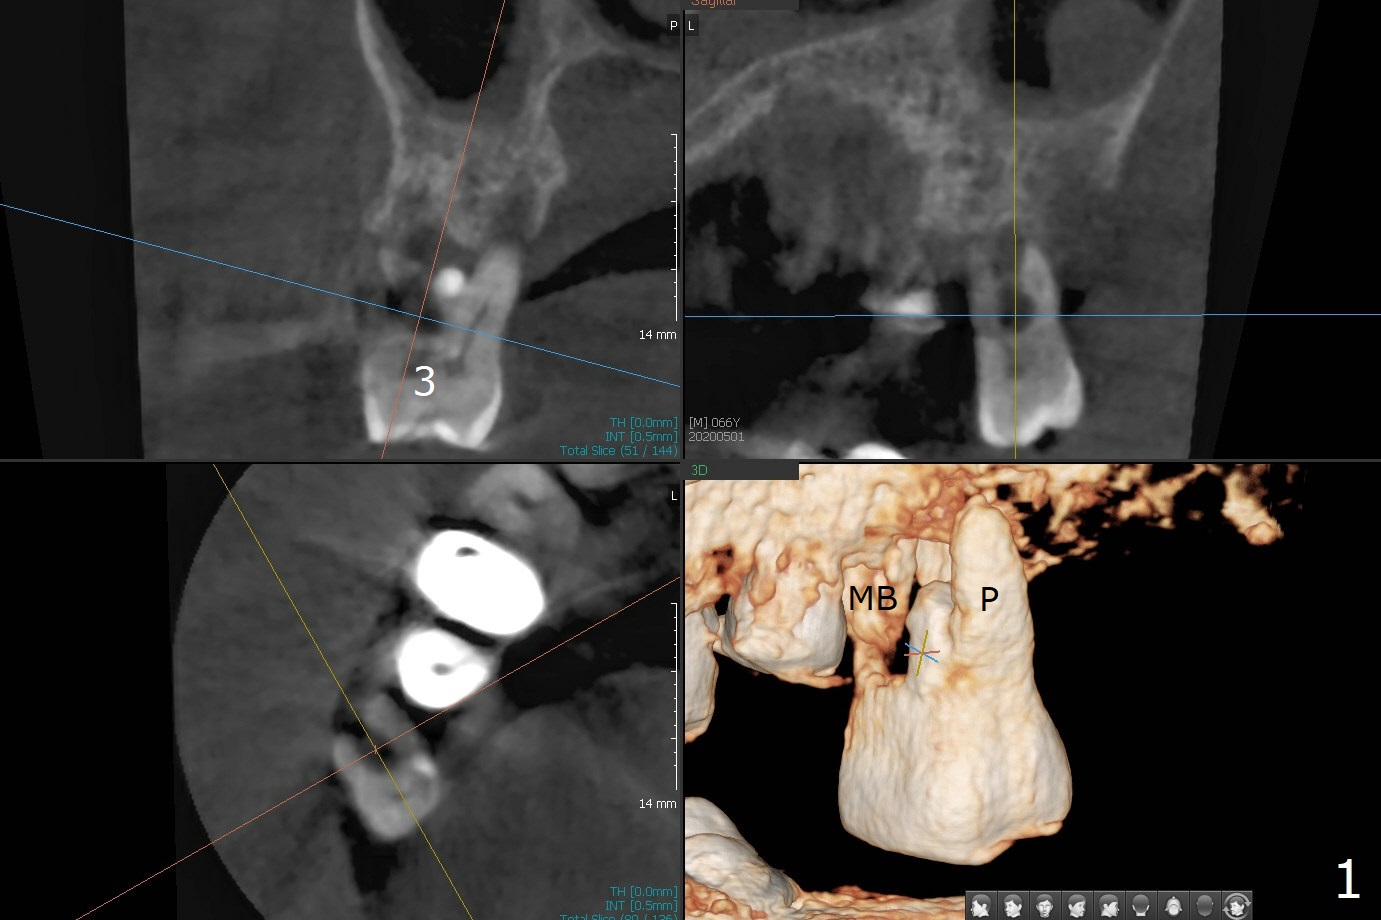

When implants at #4, 13 and 14 are placed, the patient wonders how many more implants are needed. From 0 (considering a lower RPD) to 5 (#3, 19, 20, 25 and 30). The tooth #3 seems to have periodontal-endodontic disease (Fig.1,2). Since the ridge is narrow at #19 and 20 (Fig.3), ridge split at #19 and a 1-piece implant at #20 are planned (Fig.4,5-9). The implant at #19 will be placed in an ideal prosthetic position (Fig.5). The ridge transverse bony cut will be made free hand in the middle (Fig.6,6'), followed by 2 vertical cuts and 1 apical transverse one in the 1st stage of procedure. In order to rotate the buccal block easier (Fig.6 pink curved arrow), the apical transverse cut will be wedge in shape (Fig.6 (red), 6' (double lines), 7 (black)). In the 2nd stage, the ridge top split will be extended by using a chisel (Fig.7 longer red line) and the buccal block will be pushed buccally (Fig.8). A guide will be seated to finish osteotomy (Fig.9 white) and implant placement.